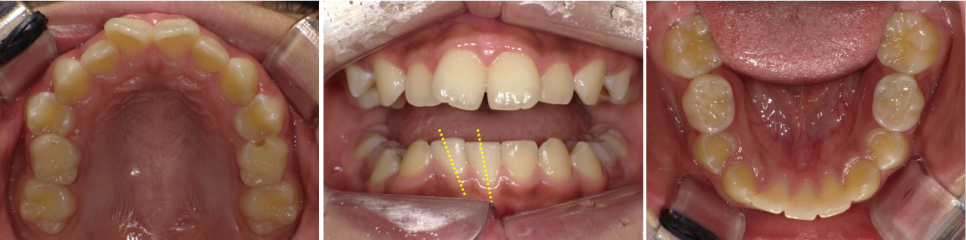

맹출 공간이 사라진 10세 여자 아이의 매복치를 판교교정치과에서 브라켓, 스크류, 고무줄 견인을 이용해 성공적으로 끌어올린 사례입니다.

성장기 부정교합 교정과 매복치 견인의 실제 과정을 확인하세요.

10세 여자 아이가 엄마 손을 잡고 내원했습니다.

“이가 나올 시기가 지난 것 같은데, 오른쪽 아래 앞니 하나가 아직도 안 나왔어요.”

방사선 촬영 결과, 아래 오른쪽 두번째 앞니가 매복되어 잇몸 안쪽 깊숙이 자리 잡고 있었고, 상방에는 치아종이 가로 막고 있었습니다.

구강 내를 보았을 때, 치아가 맹출해야 할 공간은 주변 치아가 쓰러지면서 다 차지한 상태여서 그대로 두면 자연 맹출이 불가능한 상황이었습니다.

판교교정치과 / 치료 전 구내사진

치료 계획 — ‘공간 만들기’가 먼저

매복치를 끌어올리기 위해서는 먼저 그 치아가 올라올 공간을 확보하는 것이 가장 중요했습니다.

따라서 하악에는 브라켓을 부착하고, 주변 치아를 살짝 이동시켜 매복치의 맹출 공간을 만들어주는 단계부터 시작했습니다.

매복치 상방을 가로 막고 있던 치아종은 제거했습니다.

물리적인 방해요소만 제거해도 매복치가 저절로 맹출하는 경우도 있기 때문이지요.